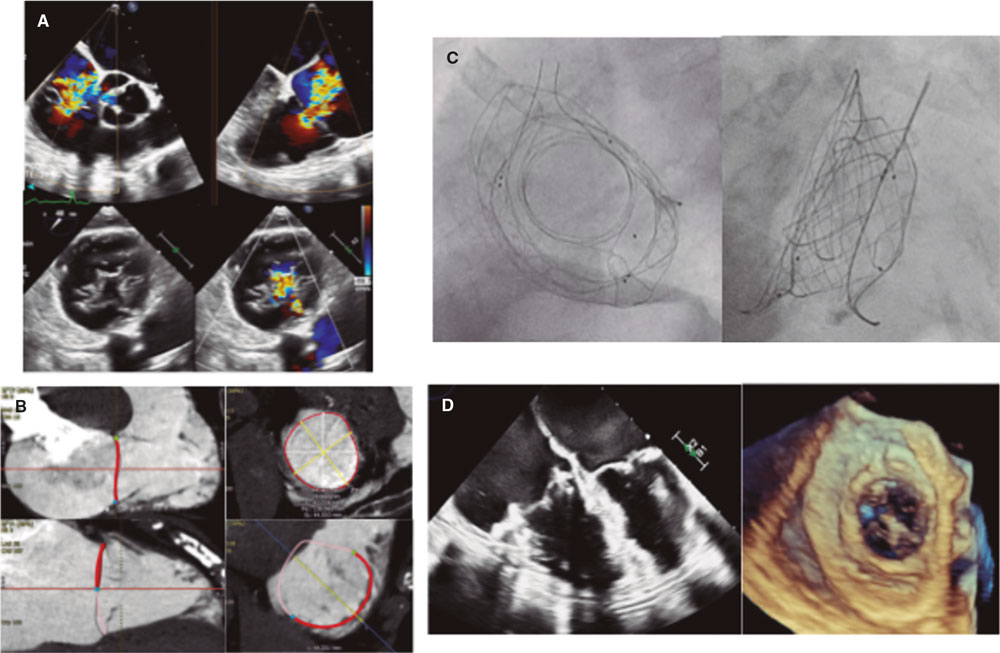

The procedure was performed in an 81-year-old woman with symptomatic disease (TRI-SCORE, 6) (New York Heart Association functional class IV, ambulatory), massive functional tricuspid regurgitation (effective regurgitant orifice width, 9 mm), and a tricuspid annulus perimeter of 137 mm (figure 2A-B). The VDyne valve (size 1 with 6% oversizing) implanted under fluoroscopic and echocardiographic guidance achieved the complete resolution of tricuspid regurgitation as confirmed by angiographic, echocardiographic, and postoperative computed tomography imaging (figure 2C-D and videos S1-S4). The patient was discharged on postoperative day 5 with marked clinical improvement, corresponding to NYHA functional class II and an increased distance on the 6-minute walk test (+90 m). This case reinforces the potential role of TTVR using dedicated valves in patients with no previous therapeutic alternatives.

Figure 2.